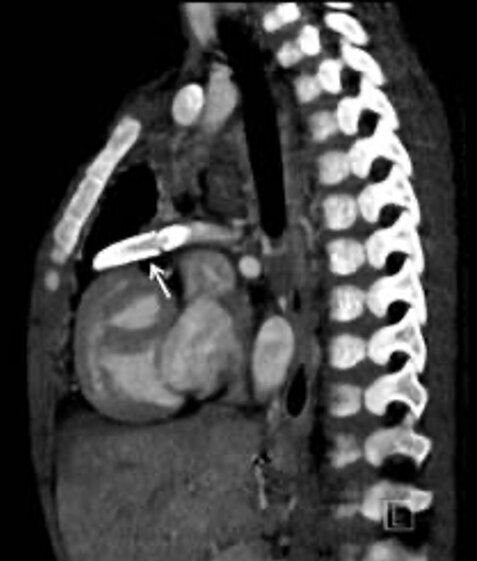

Sagittale Rekonstruktion mit operativ angelegtem Bypass (Pfeile) zwischen dem rechten Ventrikel und der Pulmonalarterie. Strahlenbelastung von 0,9 mSv.